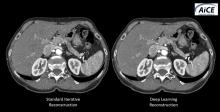

AI is also helping simplify complex tasks and help reduce the reading time on involved exams. One example of this is in 3-D breast tomosythesis with hundreds of images, which is rapidly replacing 2-D mammography, which only produces 4 images. Another example is automated image reconstruction algorithms to significantly reduce manual work. AI also is now being integrated directly into several vendors' imaging systems to speed workflow and improve image quality.